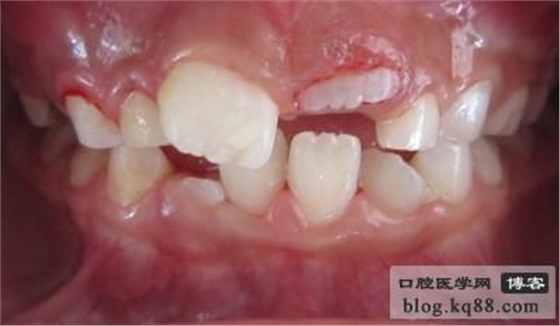

齦瓣切除助萌術(shù)后

齦瓣切除露出切端